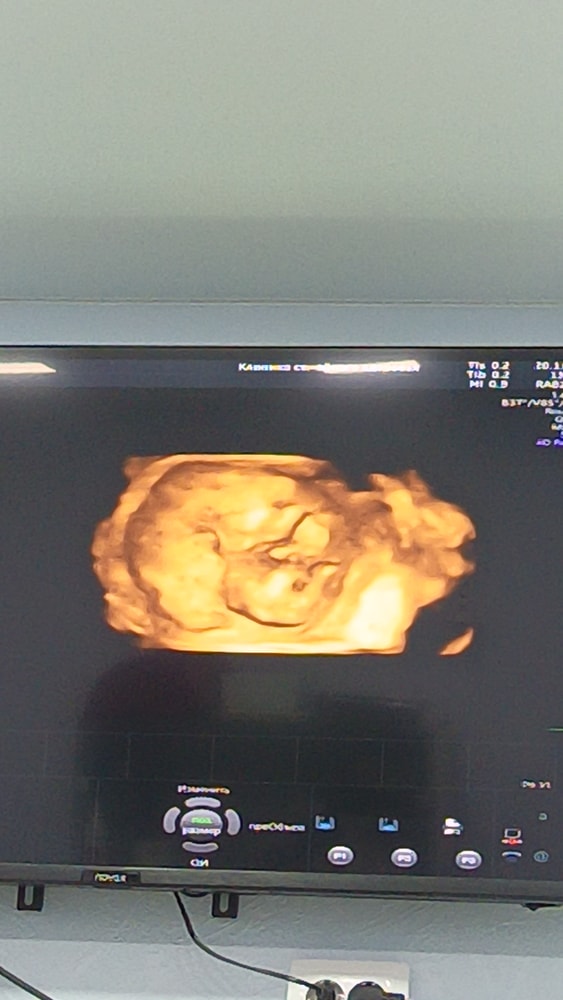

20.11 была на УЗИ, врач всё посмотрела, сказала отлично, малыш растёт. Пол врач увидела, но как мы с мужем и решили, будем делать гендер пати когда он приедет с вахты в середине декабря, эх терпения мне🤭😁уже не терпится узнать кто же там в животике живёт 😍 на УЗИ малыш как врач сказала с характером, даже не получилось сделать красивые снимки, лежит не удобно, но как по мне, эти даже ещё лучше🥰💗 сначала спал, мы его пока делали УЗИ разбудили, малыш стал кулаки показывать, попу, а в конце вообще спиной развернулся😁🤭 на секунду даже показалось что мальчишка😊 по весу написали 118 +/- грамм счастья😍 девушки, у кого примерно такой же срок, как у вас дела, как самочувствие? 😊